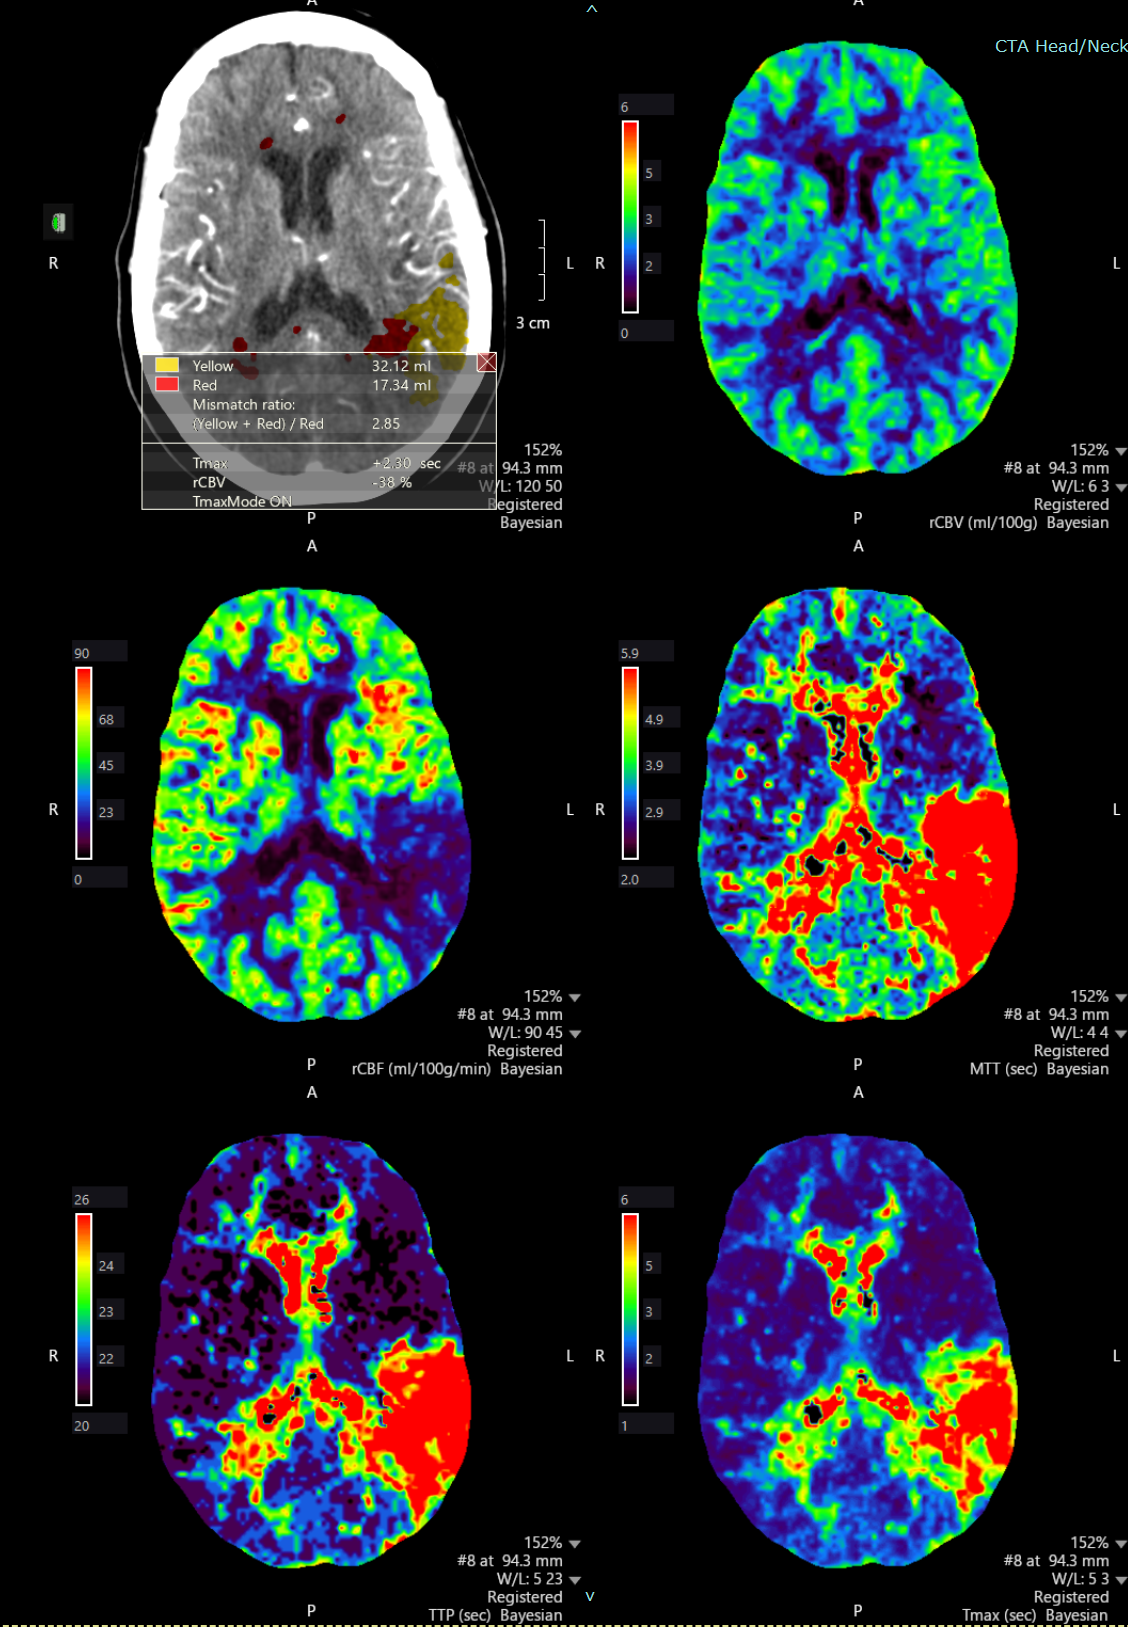

Perfusion images

Neurosurgeon Dr. Jeyan Kumar removed the blood clot from her brain by performing a thrombectomy, which involves using a small catheter to clear the vessel. After the procedure, Butcher stayed in the intensive care unit for a few days before going home with no paralysis or speech issues.